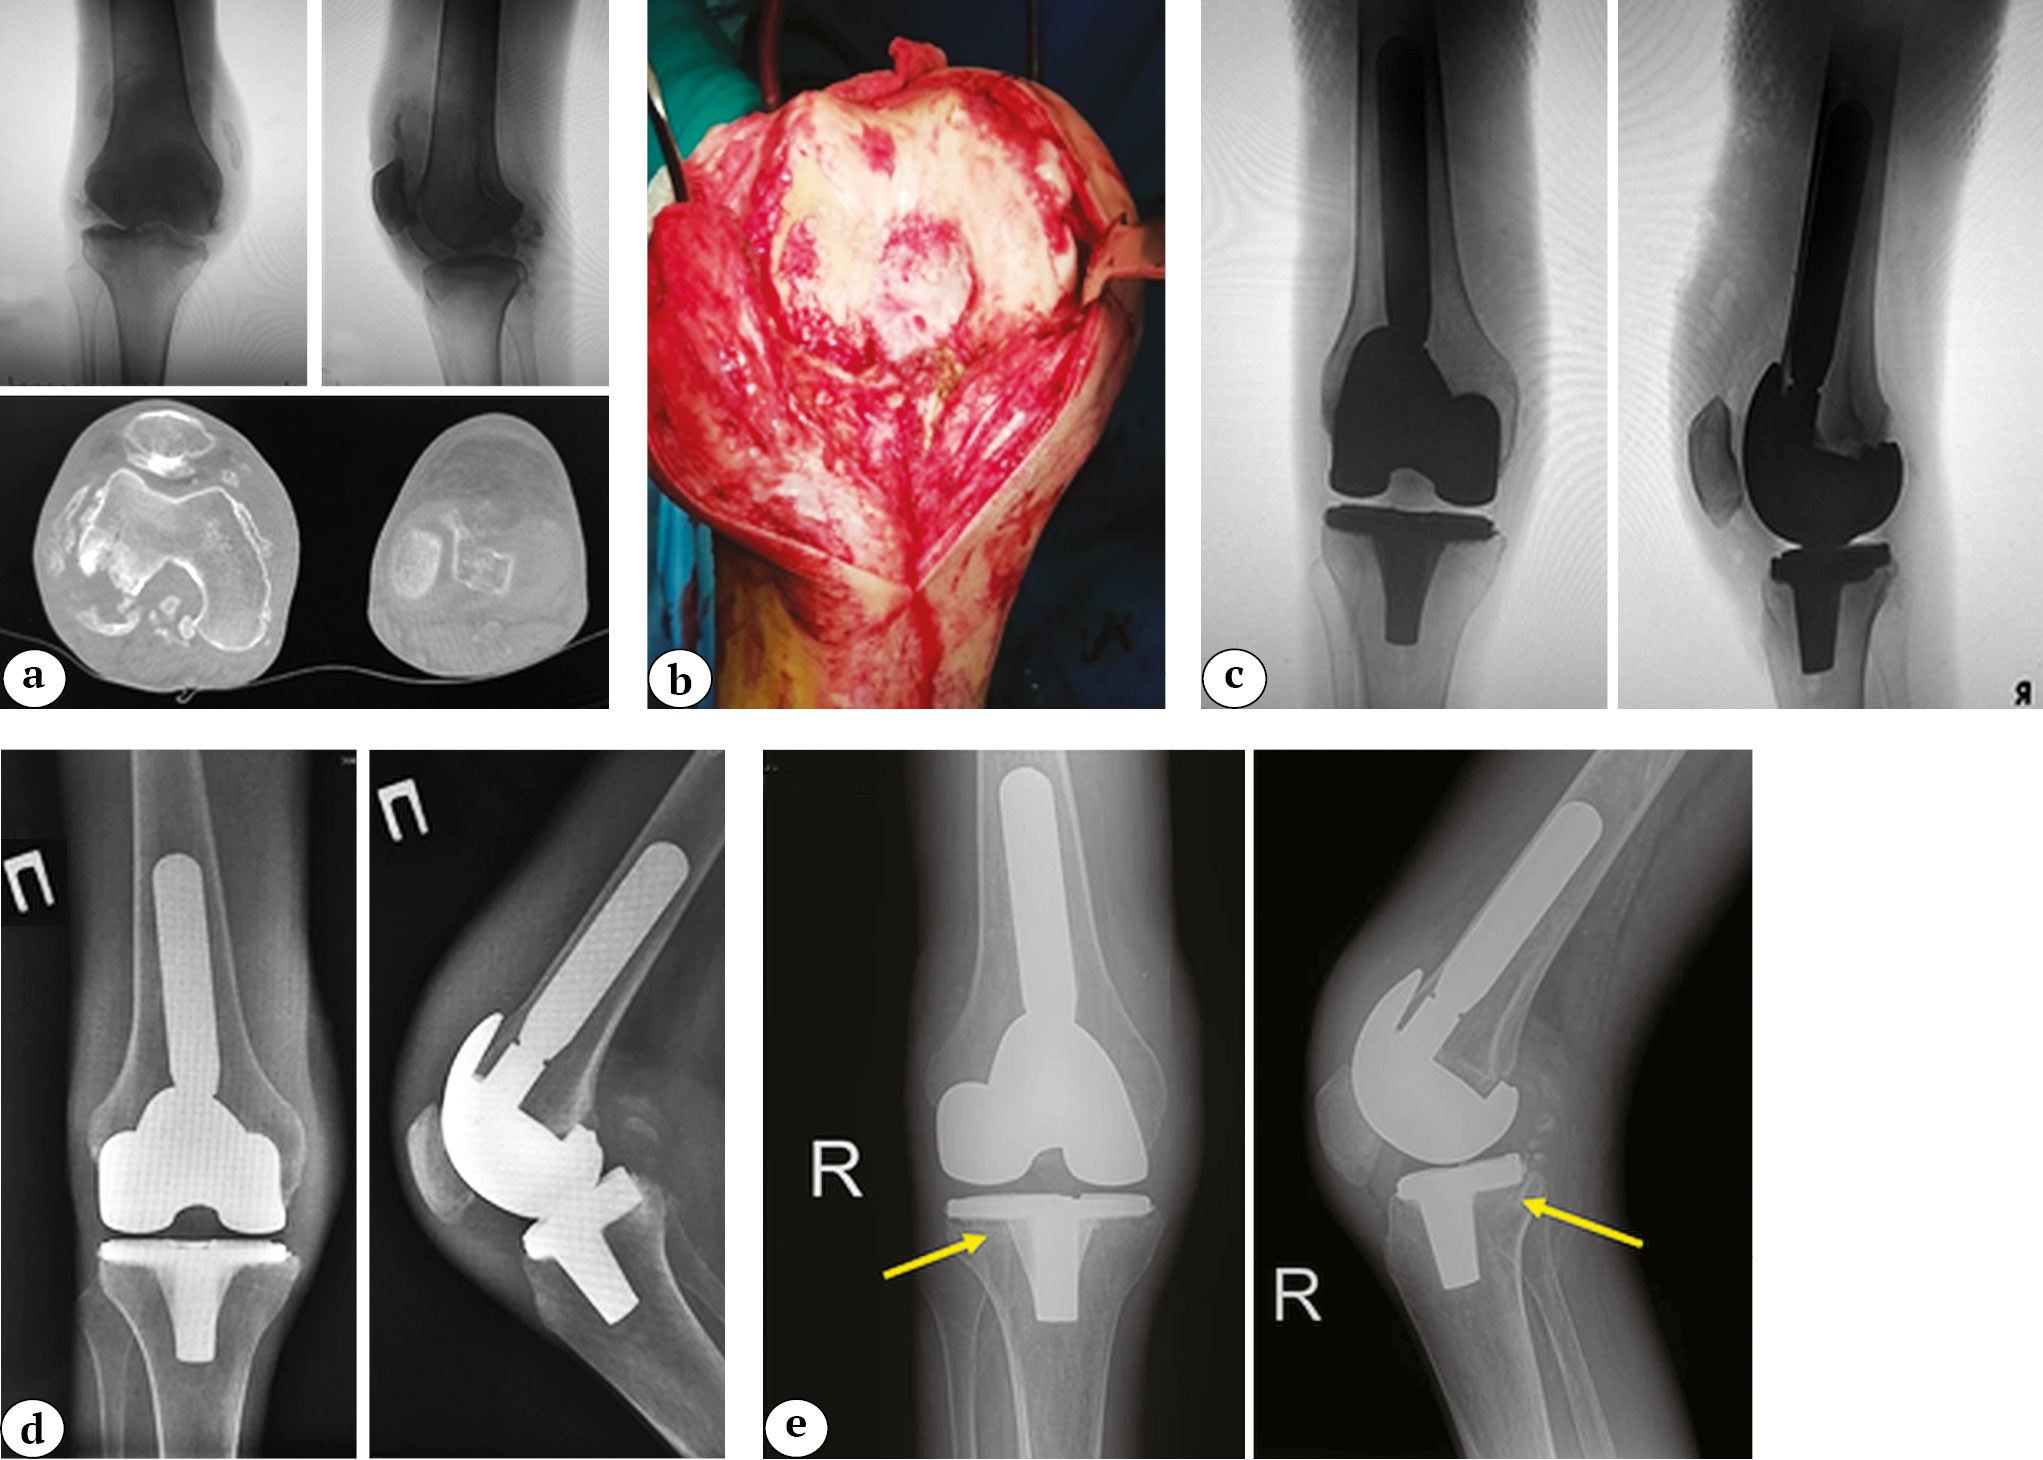

Fig. 3 (f, g). A 32-year-old man with secondary osteoarthritis of the right knee. Concomitant diseases: end-stage chronic kidney disease (5D stage), chronic hemodialysis for 7 years, type 1 diabetes: f — X-rays 3 years and 7 months after knee replacement (an articulating spacer was implanted); g — X-rays 4 years and 2 months after primary knee arthroplasty (an articulating spacer was replaced with a block spacer due to recurrent infection)